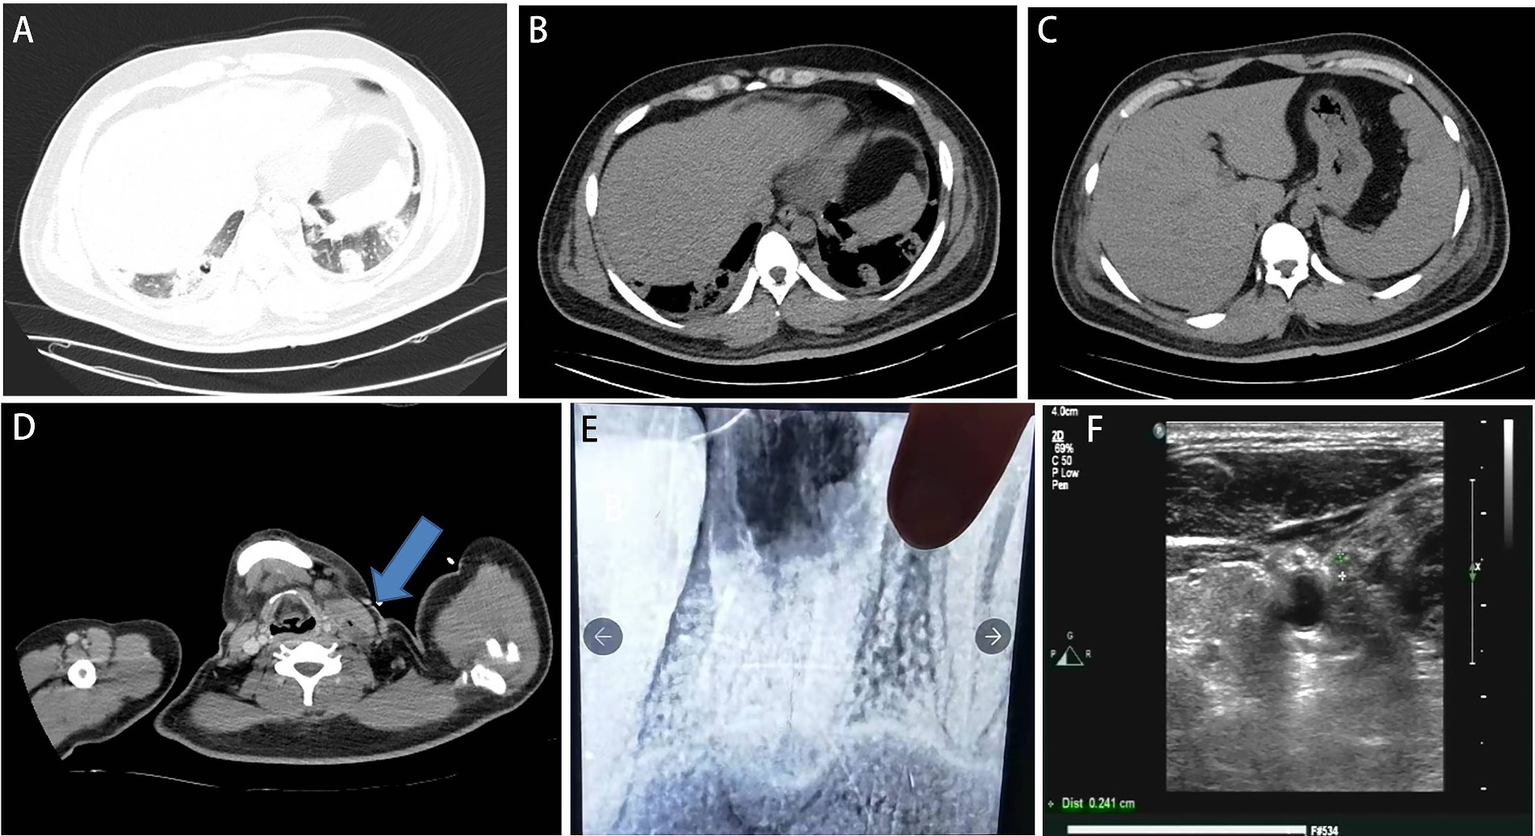

The patient developed agitation, gibberish, and emotional agitation and was transferred to the intensive care unit the next day. Since increased bilirubin combined with consciousness was observed, thrombotic thrombocytopenic purpura (TTP) cannot be excluded. ADAMTS13 activity was detected, and plasma exchange was conducted for three consecutive days. Meropenem was given due to its ability to penetrate the blood–brain barrier. The laboratory tests showed triglyceride of 4.06 mmol/L, high-density lipoprotein cholesterol (HDL-C) of 0.07 mmol/L, glycosylated hemoglobin of 8.7%, fasting blood glucose of 10.51 mmol/L, suggesting diabetes and hyperlipidemia. On the 5th day of admission, the bacterial blood culture showed anaerobic Gram-negative bacilli. However, the specific pathogen and drug susceptibility tests were not conducted. The mNGS test showed Fusobacterium necrophorum (Identification confidence 99%, 13,723 reads; genus Fusobacterium, relative abundance 85.6%, and 14,370 reads) (Figure 1). The patient was conscious and complained of pain in the left neck and shoulder and limited activities. The enhanced CT scan showed that the left proximal jugular vein and brachiocephalic vein had a strip filling defect, indicating thrombosis. The surrounding soft tissue was swollen, with a small amount of gas accumulation, multiple nodules, and cavitary lesions in both lungs increased accompanied by the consolidation of some lung tissues (Figures 2A–D). Based on these indications, Lemierre’s syndrome was diagnosed. Nadroparin calcium was administered as an anticoagulant. ADAMTS13 activity showed 26%, excluding TTP. The infectious indicators of the patient decreased, while the liver and kidney function improved. On the 9th day of admission, the patient was transferred to the infectious disease ward. Rivaroxaban was given as an anticoagulant. On the 18th day of admission, the antibiotic was changed to cefoperazone/sulbactam sodium 3 days before discharge. After repeated medical history queries, the patient mentioned he underwent root canal treatment on the left maxillary first premolar 20 years ago, and the fillings in the tooth fell out about 2 weeks before onset. Rivaroxaban was continued after discharge. Then he took an oral X-ray at the dentist’s clinic (Figure 2E). The chest CT scan was found to be normal when taken 2 months after discharge. However, the ultrasound showed that the thrombus in the neck had not subsided (Figure 2F). The anticoagulant drugs were discontinued.

Figure 2

(A–D) Computed tomography scan at admission to the intensive care unit. (A,B) It showed bilateral pulmonary nodules and cavities. (C) Decreased liver density. (D) Left internal jugular vein thrombosis with gas accumulation (blue arrow). (E) X-ray after charge in a dental clinic. A cavity was at the left maxillary first premolar. (F) 2 months after discharge, the ultrasound showed that the thrombus in the neck had not subsided.